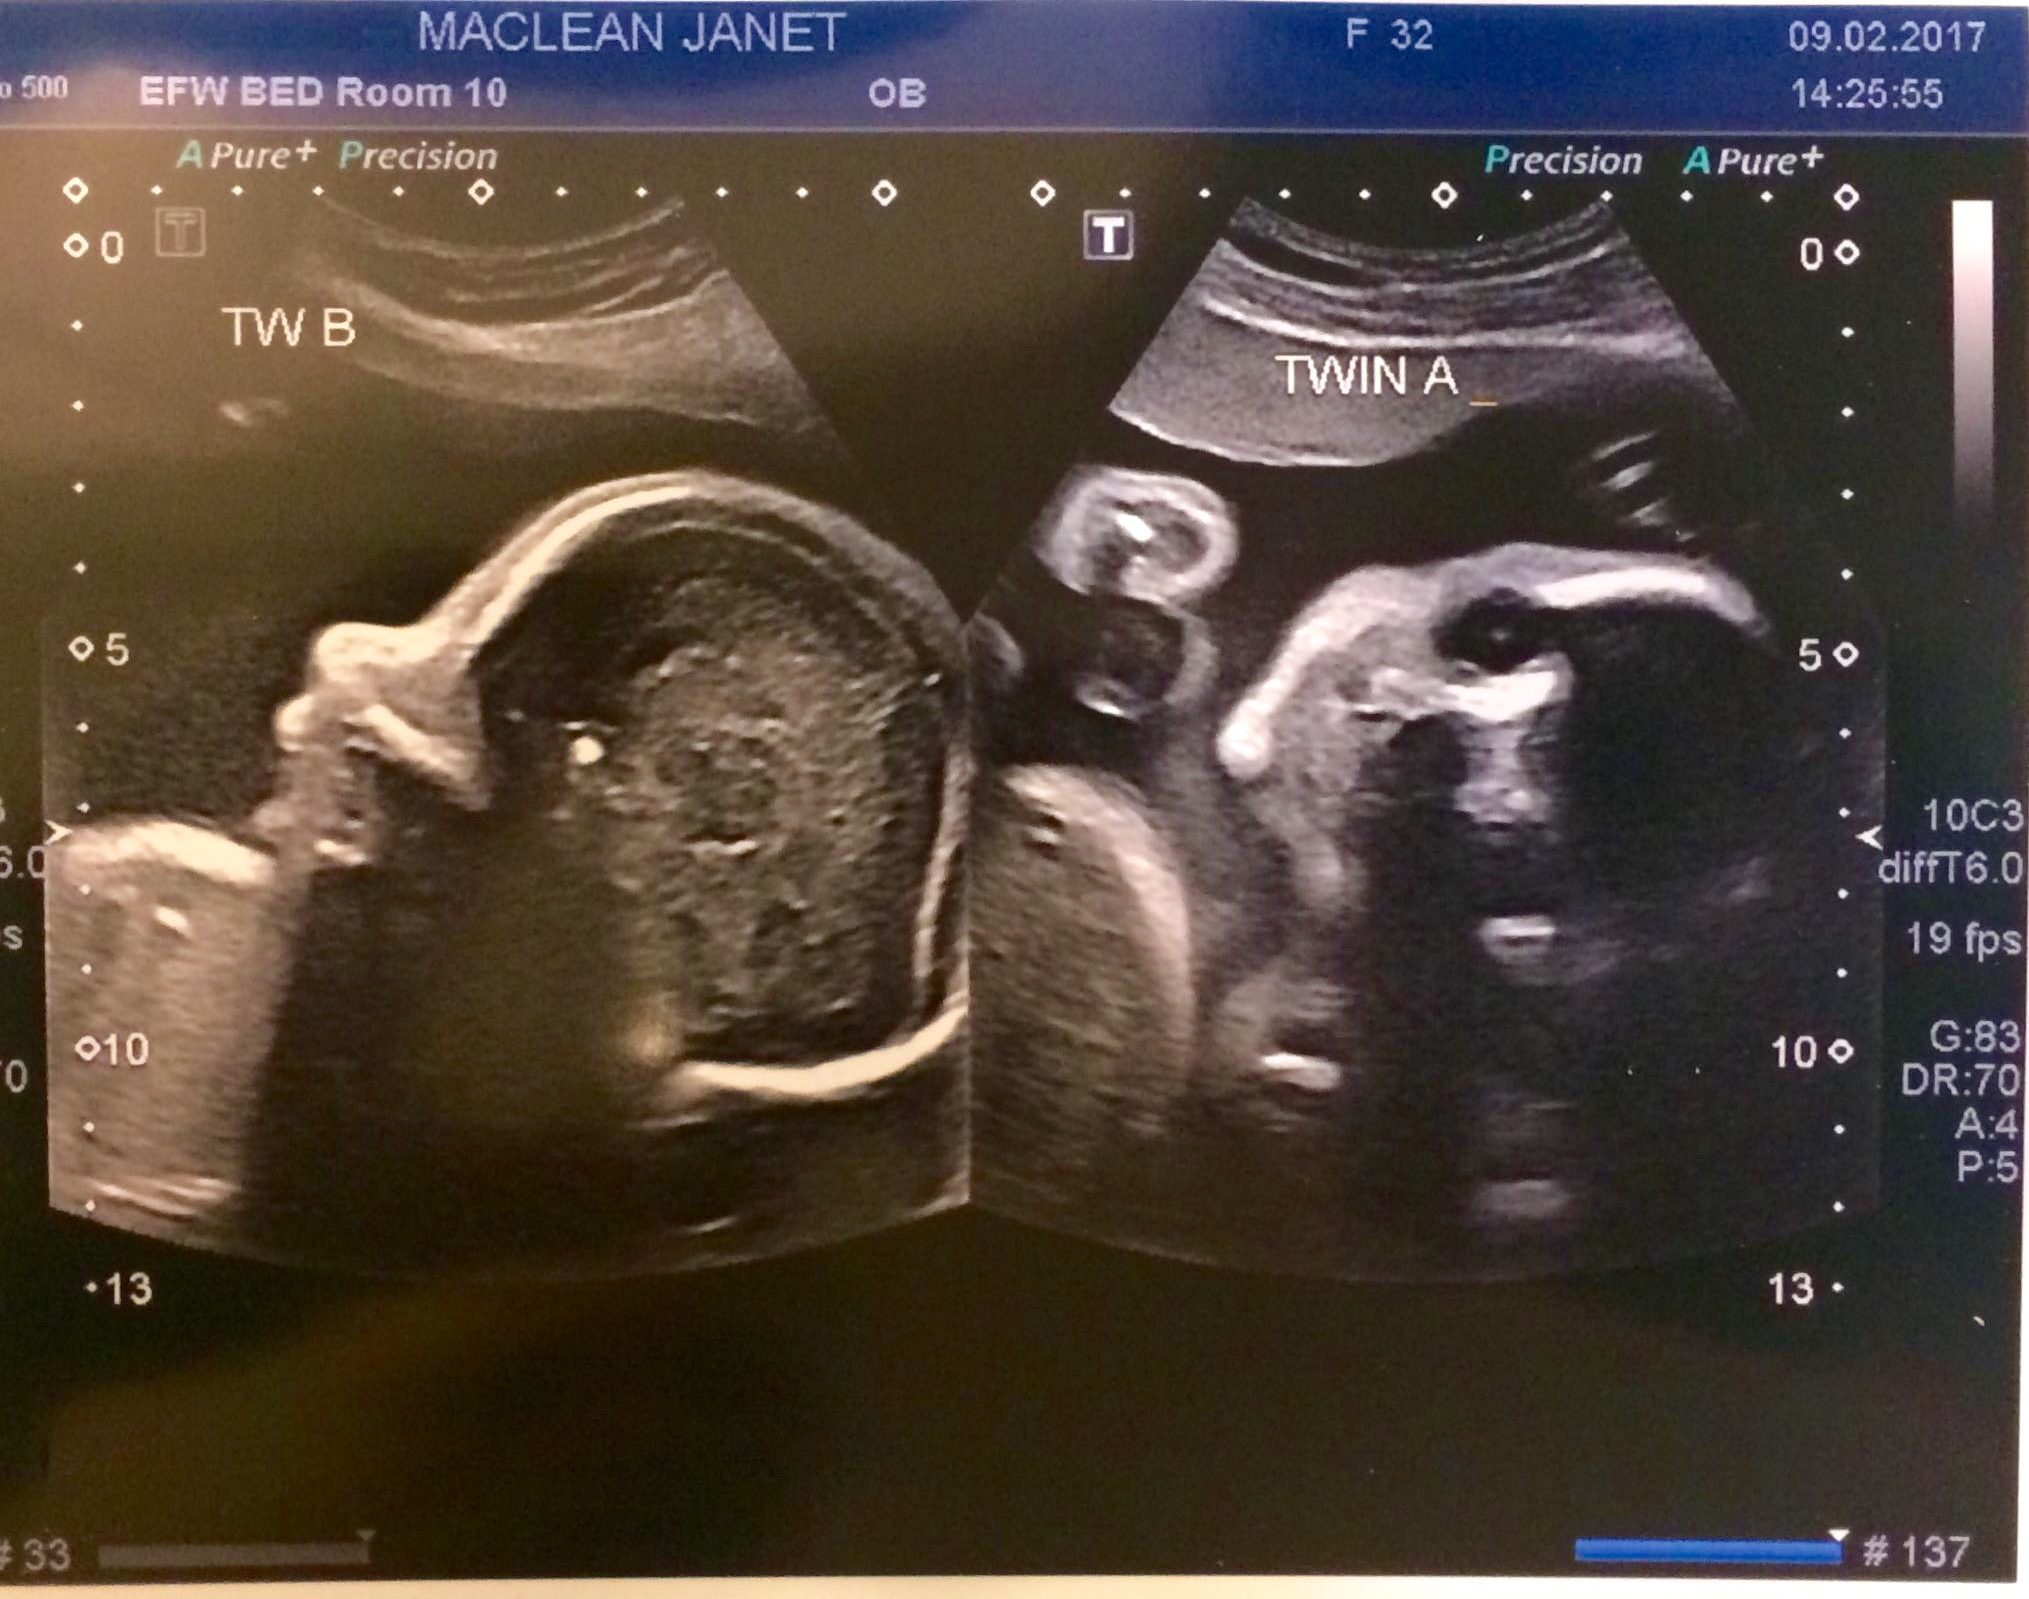

This is a picture of Baby boy spinal column (his face was towards my spine and the technician couldn't get a good profile picture- so I asked for a picture of the spine, I like how defined it is). The other picture is of the baby girl head on, it's hard to make out the features though!

Baby girl is 2 pounds 12 ounces with HR of 136

Baby boy is 2 pounds 8 ounces with a HR of 131. He has moved back to the breech position (head up and feet down).

Everything is on track with growth and development